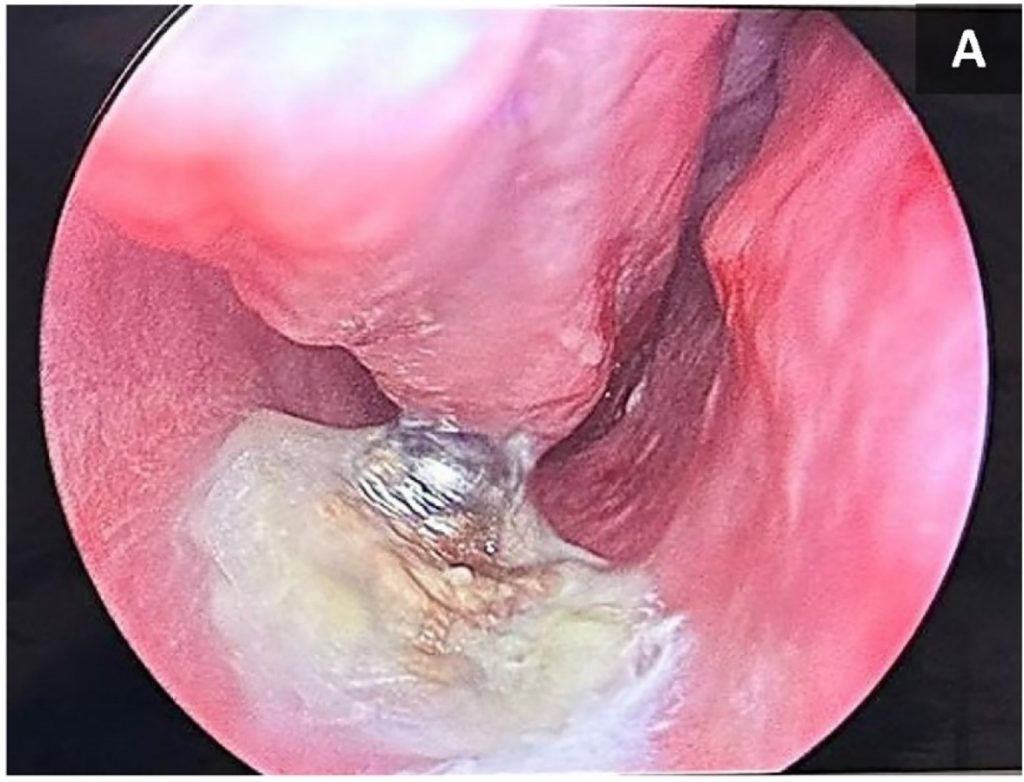

The journal explained: “The object was partially covered with mucus and possibly some crusted material and had a shiny appearance, indicating a metallic nature.

“The surrounding bony structures appeared normal.